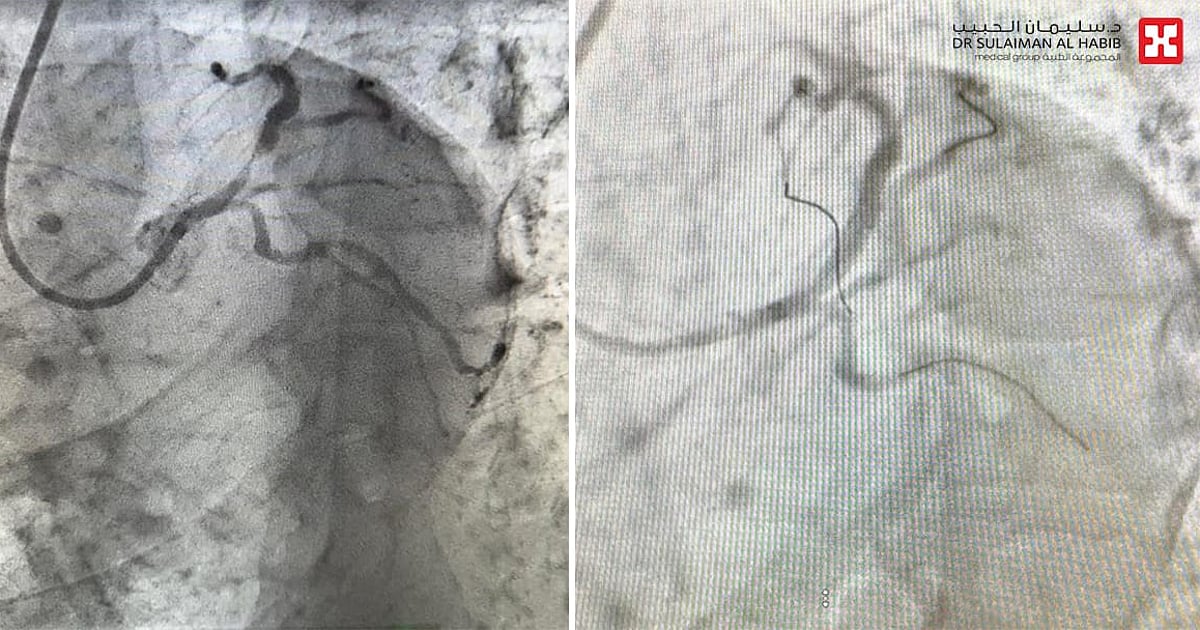

مستشفى الدكتور سليمان الحبيب بالمحمدية في جدة يُنقذ مراجع مصاب بانسداد حاد نسبته “99%” بالشريان التاجي الأيسر

بفضل من الله – أنقذ مستشفى الدكتور سليمان الحبيب بالمحمدية في جدة، حياة رجل عمره “65” عاماً، ويعاني من جلطة قلبية حادة، وانسداد بنسبة “99%” في الشريان التاجي الأيسر النازل. وأجرى له فريق طبي قاده د. أنس الحربي استشاري أمراض القلب وقسطرة القلب التداخلية، عملية قسطرة ناجحة، أنقذت حياته خلال فترة وجيزة من لحظة وصوله إلى الطوارئ.